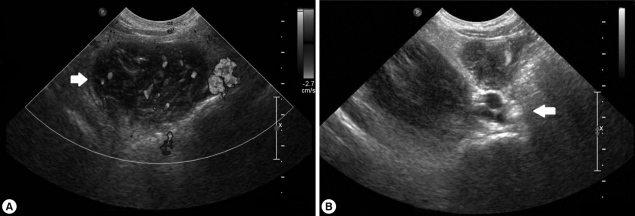

On admission, her vital signs were as follows: body temperature, 37.8℃; heart rate, 90/min; respiratory rate, 24/min; and blood pressure, 100/70 mmHg. On examination, she looked very ill and her breathing sounds were decreased on both sides of the lower chest. Moderate tenderness was detected in the right flank and the right inguinal area. A chest radiograph indicated pleural effusion (Fig. 1), and abdominal sonography revealed an inflammatory lesion in the right psoas muscle (Fig. 2). Her total white blood cell (WBC) count was 26,900 cells/mm3, hemoglobin level was 10.7 g/dl, erythrocyte sedimentation rate (ESR) was 75 mm/hr, and C-reactive protein concentration was 71 mg/dl. The patient also presented with hypereosinophilia (66%), and the total serum IgE value higher than 2,500 IU/ml. Because her dietary history and laboratory findings were indicative of a parasitic infection, we performed a serum antibody test using ELISA and examined her stool, sputum, and pleural fluid specimens [11]. No evidence of parasite eggs in the stool or sputum specimen was obtained, but ELISA was positive for P. westermani in the serum, with an optical density (OD) of 0.619 (cut-off OD: 0.255). The pleural fluid obtained by thoracentesis revealed the following findings: WBC, 26,200 cells/mm3 (neutrophils, 25%; lymphocytes, 72%); pH, 7.129; proteins, 8.2 g/dl; albumin, 2.1 g/dl; glucose, 5 mg/dl; and turbid appearance. Gram staining, culture studies, and tuberculosis- PCR (TB-PCR) in the pleural fluid, however, were negative.

Analysis of the drained pleural fluid showed the following results: WBC, 250 cells/mm3 (neutrophils, 8%; lymphocytes, 49%); pH, 7.164; protein, 9.8 g/dl; albumin, 2.7 g/dl; glucose, 4 mg/dl; and amber colored appearance. Gram staining and culture studies of the pleural fluid were negative, but P. westermani-specific IgG antibody was strongly positive in the pleural fluid, with an OD of 1.576 (cut-off OD: 0.002). Abdominal sonography revealed a smaller, albeit still existing, inflammatory lesion in the right psoas muscle (Fig. 3B). The patient was treated again with a third cycle of praziquantel therapy. After 4 days, the catheter for draining pleural fluid was removed, and she was discharged.

The major symptoms of paragonimiasis are cough, hemoptysis, and dyspnea; some of these overlap with symptoms of tuberculosis and other pulmonary disorders. Pulmonary infiltrates, effusion, nodules, or lesions are also very common [14, 15], and ectopic locations of flukes include the pleura, abdominal wall, viscera, and brain. In our case, the patient complained of abdominal pain, especially in the right flank and right inguinal area but had no cough, dyspnea, or chest pain. The chest radiograph revealed pleural effusion, and abdominal sonography showed a low-echoic lesion with inflammation of the surrounding fat in the psoas mucle. This lesion is presumed to be due to adult flukes, which are present in loosely formed cysts in the psoas muscle.